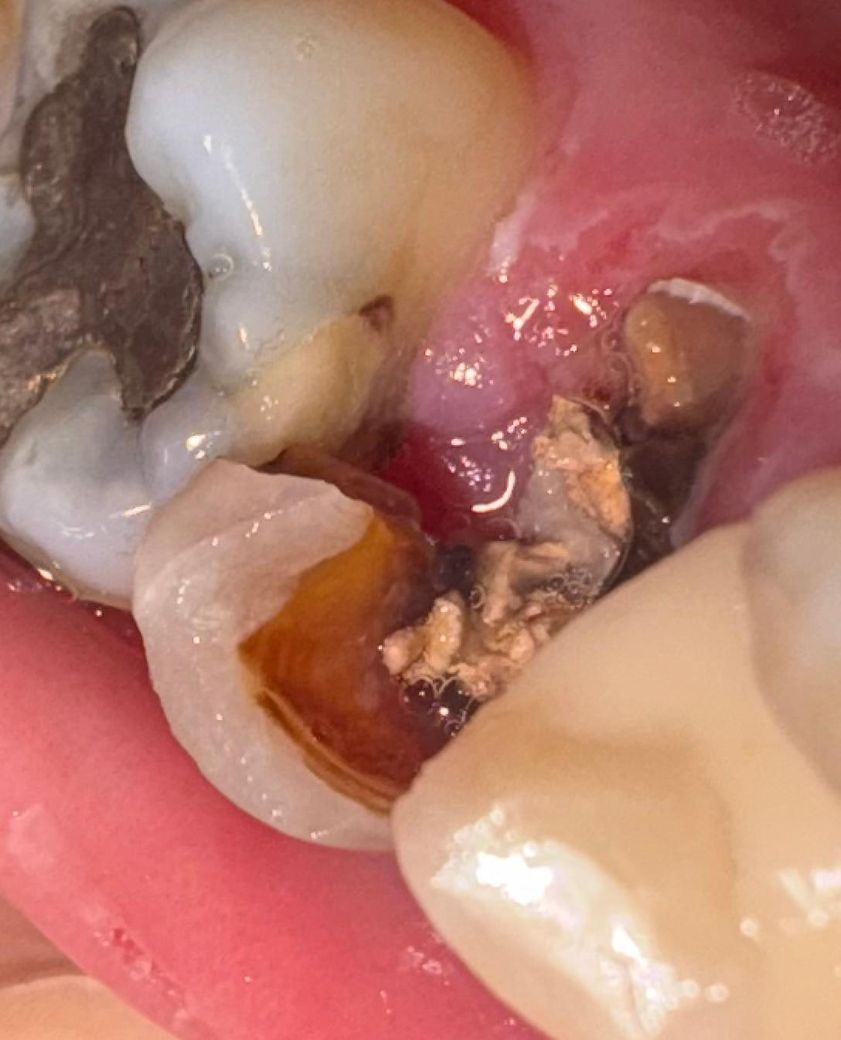

• 3번 째 사진

사진에 보이는 정도의 치아 상태라면 발치를 하시고 나서 임플란트를 하셔야될것같습니다.

사진을 봤을 경우 충치나 파절된 부위가 치조골 부위에 근접한 것으로 보입니다.

이런경우에는 발치를 하는것이 예후가 더 좋을수 있습니다.

2. 저정도 파절이면 남은 치아가 너무 부족해서 뭘 하기가 난감합니다

3. 대학치과병원 보존과에 가서 잇몸 및 골 절제술 통한 치아 길이 확보 + 포스트와 코어 보강 + 크라운 상담 받아보세요